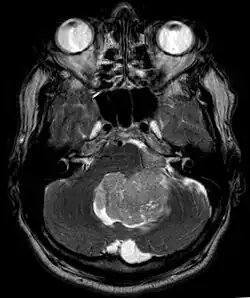

In Kernspintomografie-Aufnahmen des Kopfes stellt sich das Ependymom typischerweise als umschriebene Läsion mit Bezug zum Ventrikelsystem dar, die ein heterogenes Signalmuster mit zystischen Anteilen aufweist sowie mäßig und girlandenartig Kontrastmittel anreichert. In 50 % sind in der Schnittbildgebung Verkalkungen zu erkennen. Zytologische Untersuchung der Cerebrospinalflüssigkeit sowie Tumorbiopsie können zur Diagnosefindung beitragen.